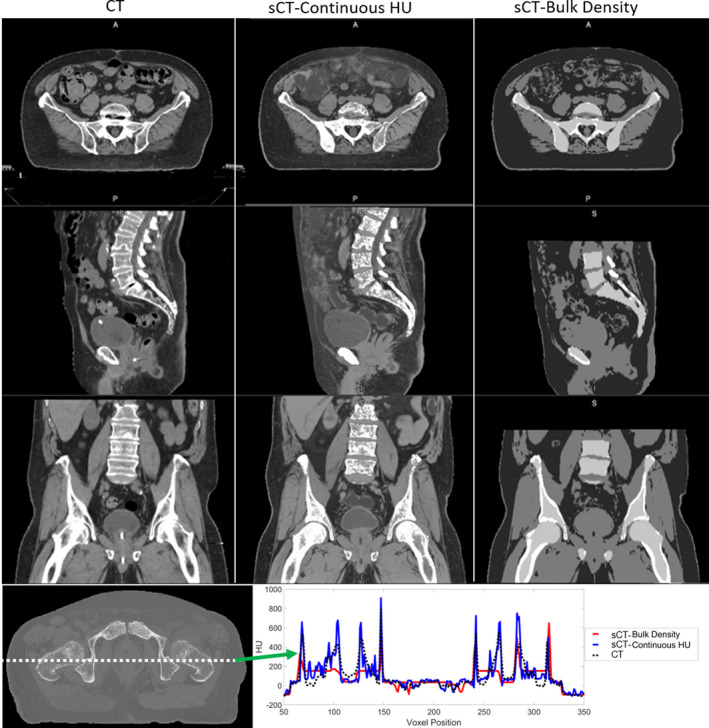

Figure 2 shows the original CT, MRCAT general pelvis sCT‐cHU, and MRCAT prostate sCT‐BD, and an example HU profile comparing the three images from an example case. sCT‐cHU looks significantly more similar to the planning CT, and offers a longer FOV in the SI direction, when compared with the widely utilized sCT‐BD. Example HU profile of all three images overlaid also further demonstrates that sCT‐cHU more closely agrees with that of the CT.

FIG. 2.

An example case comparing planning CT, continuous HU synthetic CT and the bulk density synthetic CT. HU profile comparison between CT and the continuous HU and bulk density synthetic CTs. CT: black dashed line, continuous HU synthetic CT: blue, bulk density synthetic CT: red (CT: computed tomography, HU: Hounsfield unit, A: anterior; P: posterior, S: superior, I: inferior).

MAE of bone, soft tissue, and total body of the sCT‐BD approach compared with the sCT‐cHU approach is shown in Table 3. sCT‐cHU has lower MAE values than that of sCT‐BD for all compared tissue volumes as expected, particularly significant decrease of up to 40.3 HU was shown for the MAE in bone. A HU profile comparison of the two methods and the CT is also shown in Fig. 2 for an example case, where a closer agreement between the sCT‐cHU to CT can be seen.